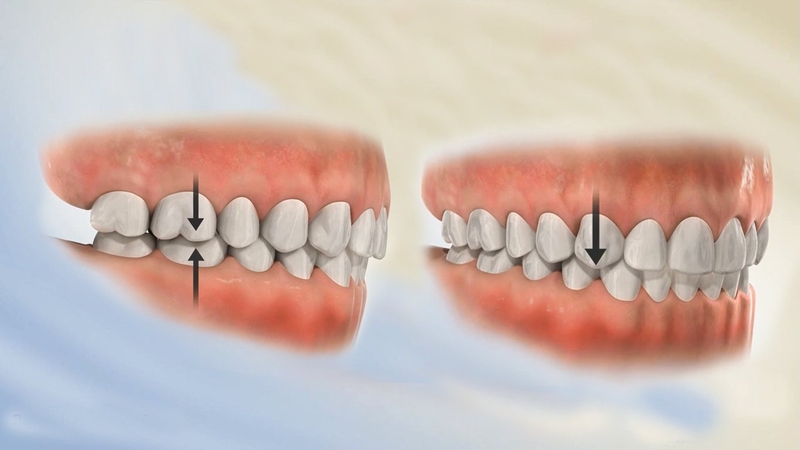

Nong hàm thường được chỉ định với những trường hợp người có vòng hàm quá hẹp. Cách xác định vòng hàm hẹp được thực hiện dựa trên tương quan giữa vòm hàm với cấu trúc tổng thể của khuôn mặt chứ không có chỉ số cụ thể nào.

Để xác định vòng hàm có bị hẹp hay không, bác sĩ sẽ thăm khám trực tiếp và chụp X-quang để xác định. Chính vì vậy nếu xác định bạn có vòng hàm quá hẹp thì bác sĩ sẽ chỉ định kết hợp nong hàm để tạo sự cân đối cho khuôn mặt.

Hàm méo, lệch là trường hợp khó nhất khi nong hàm. Lúc này, bác sĩ cần sử dụng lực nong rộng một bên để tương xứng với bên còn lại, giúp khuôn mặt cân đối hơn.